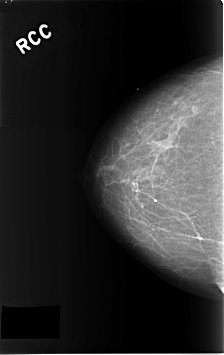

C_0303_1.RIGHT_MLO

RIGHT_CC LINES 4608 PIXELS_PER_LINE 2904 BITS_PER_PIXEL 12 RESOLUTION 50 NON_OVERLAY